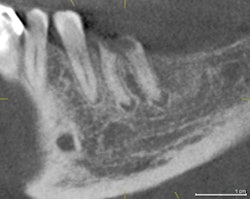

On review of his 3D images, it became apparent that neglecting to intervene earlier had allowed periodontal hard-tissue breakdown to progress to an unmanageable state for tooth #3 and possibly for tooth #14. Tooth #19 was deemed hopeless and could be extracted, bone grafted, implanted, and restored, as the bone volume could be regenerated to receive an implant.

The incidental findings in this scan were multiple: the total resorption of palatal bone in the area of tooth #14 with periapical pathology, and the complete destruction of alveolar support for tooth #3, which was close to undermining the apices of the adjacent premolar #4. The treatment plan was formulated based the images shown.